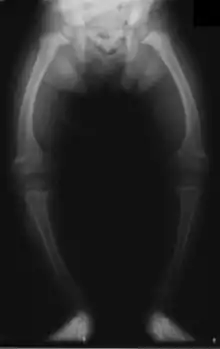

Primidone, along with phenytoin and phenobarbital, is one of the anticonvulsants most heavily associated with bone diseases such as osteoporosis, osteopenia (which can precede osteoporosis), osteomalacia, and fractures.[32][33][34] The populations usually said to be most at risk are institutionalized people, postmenopausal women, older men, people taking more than one anticonvulsant, and children, who are also at risk of rickets.[32] Bone demineralization is suggested to be most pronounced in young people (25–44 years of age),[33] and one 1987 study of institutionalized people found that the rate of osteomalacia in the ones taking anticonvulsants—one out of 19 individuals taking an anticonvulsant (vs. none among the 37 people taking none) —was similar to that expected in elderly people. The authors speculated that this was due to improvements in diet, sun exposure, and exercise in response to earlier findings, and/or that this was because it was sunnier in London than in the Northern European countries, which had earlier reported this effect.[34] In any case, the use of more than one anticonvulsant has been associated with an increased prevalence of bone disease in institutionalized epilepsy patients versus institutionalized people who did not have epilepsy. Likewise, postmenopausal women taking anticonvulsants have a greater risk of fracture than their drug-naive counterparts.[32]

Anticonvulsants affect the bones in many ways. They cause hypophosphatemia, hypocalcemia, low vitamin D levels, and increased parathyroid hormone. Anticonvulsants also contribute to the increased rate of fractures by causing somnolence, ataxia, and tremor, which would cause gait disturbance, further increasing the risk of fractures on top of the increase due to seizures and the restrictions on activity placed on epileptic people. Increased fracture rate has also been reported for carbamazepine, valproate, and clonazepam. The risk of fractures is higher for people taking enzyme-inducing anticonvulsants than for people taking enzyme-non-inducing anticonvulsants.[33] In addition to all of the above, primidone can cause arthralgia.[25]